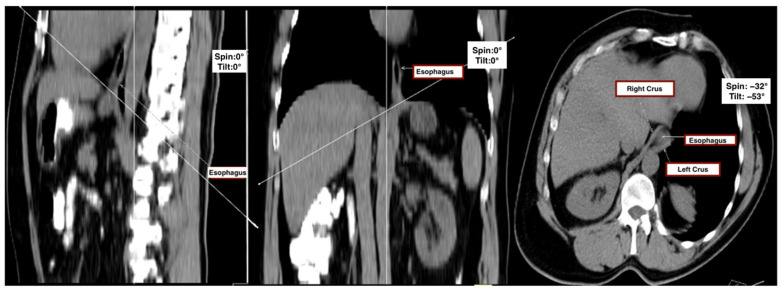

Methods: In this retrospective, single-center study, 100 adult patients (50 with thoracic kyphosis, defined as a Cobb angle of ≥50° and 50 age- and sex-matched controls) underwent multidetector CT (MDCT). Hiatal surface area (HSA) was measured on a standardized oblique axial plane aligned with the diaphragmatic crura. Correlation and multivariable regression analyses were performed to assess relationships between Cobb angle and HSA.